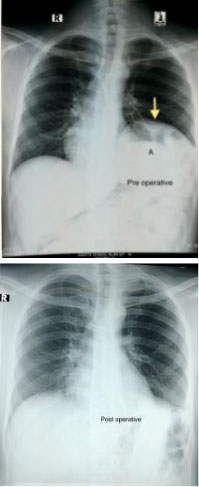

Figure 8: (Top) Pre-operative CXR showing displacement of the stomach (A) in the mediastinum (arrow). (Bottom) Postoperative CXR after reduction of hernia and correction of diaphragmatic defect.